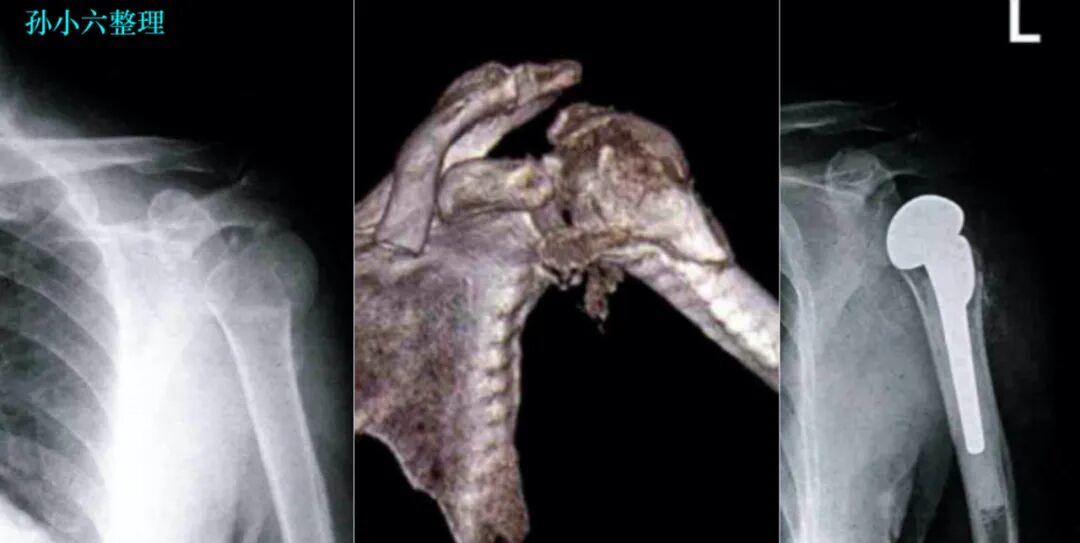

肱骨近端骨折

肱骨近端骨折常用的分型是 Neer 分型。

肱骨近端骨质疏松性骨折,因骨质条件欠佳而常导致复位和固定困难,尤其是粉碎性骨折,可出现肱骨头坏死、肩关节脱位或半脱位,严重影响关节功能。

医疗康复包括什么骨质疏松性骨折:诊断、治疗和康复一文整理!_https://www.jmylbn.com_新闻资讯_第31张

临床可根据 X 线检查判断骨折类型,通过 CT 扫描明确主要骨块移位及压缩程度,而 MRI 则有助于判断肩袖损伤。

手术治疗方式:

闭合复位经皮穿针固定;切开复位内固定;髓内钉内固定;肱骨头置换

医疗康复包括什么骨质疏松性骨折:诊断、治疗和康复一文整理!_https://www.jmylbn.com_新闻资讯_第32张

医疗康复包括什么骨质疏松性骨折:诊断、治疗和康复一文整理!_https://www.jmylbn.com_新闻资讯_第33张